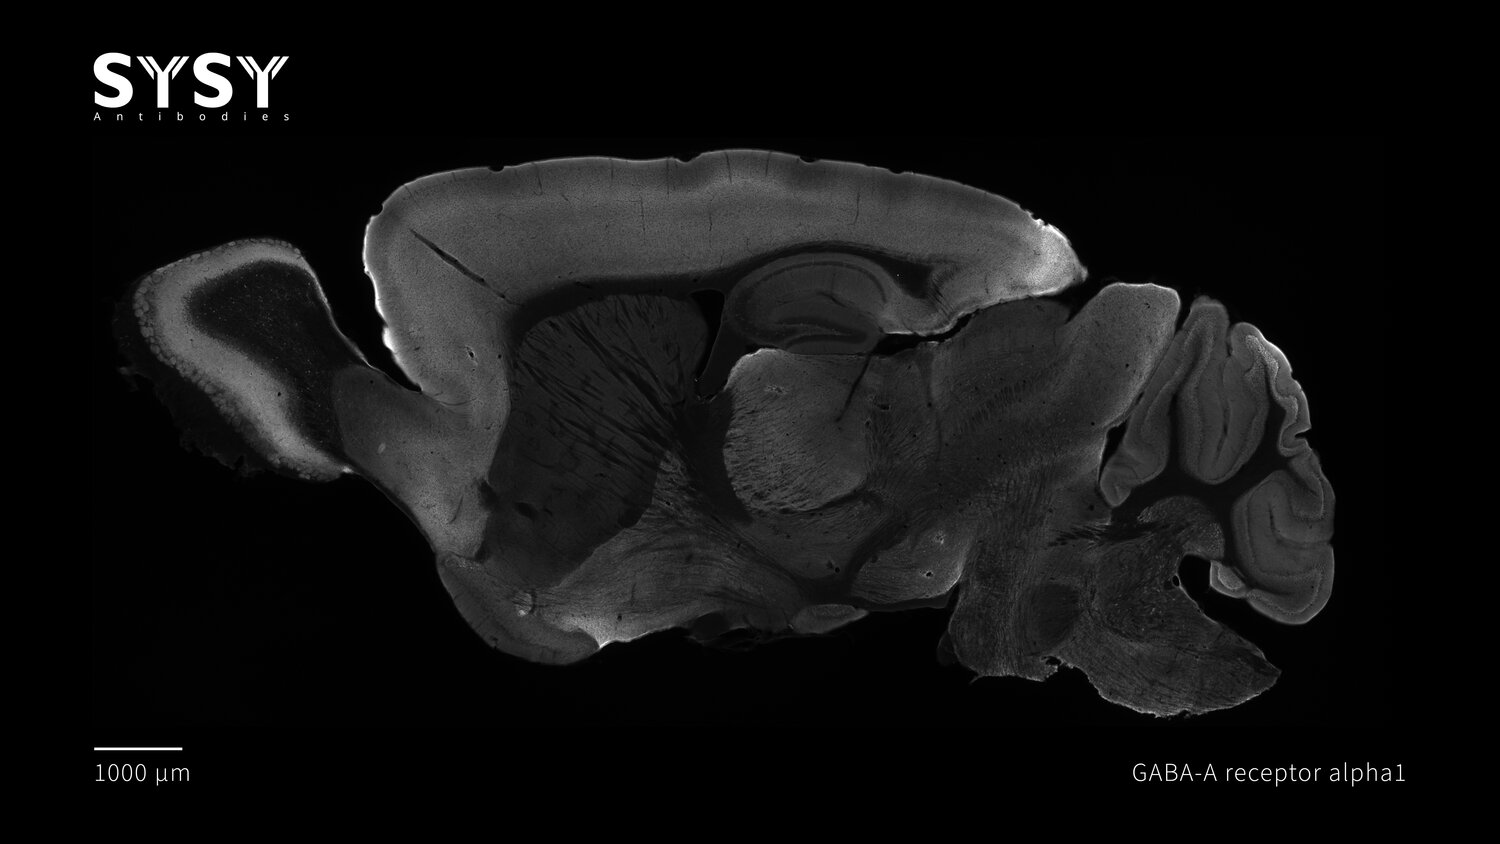

GABA-A receptor alpha1

Indirect immunostaining of a formaldehyde fixed sagittal mouse brain section with mouse anti-GABA-A receptor alpha1 antibody (cat. no. 224 211, dilution 1 : 500).